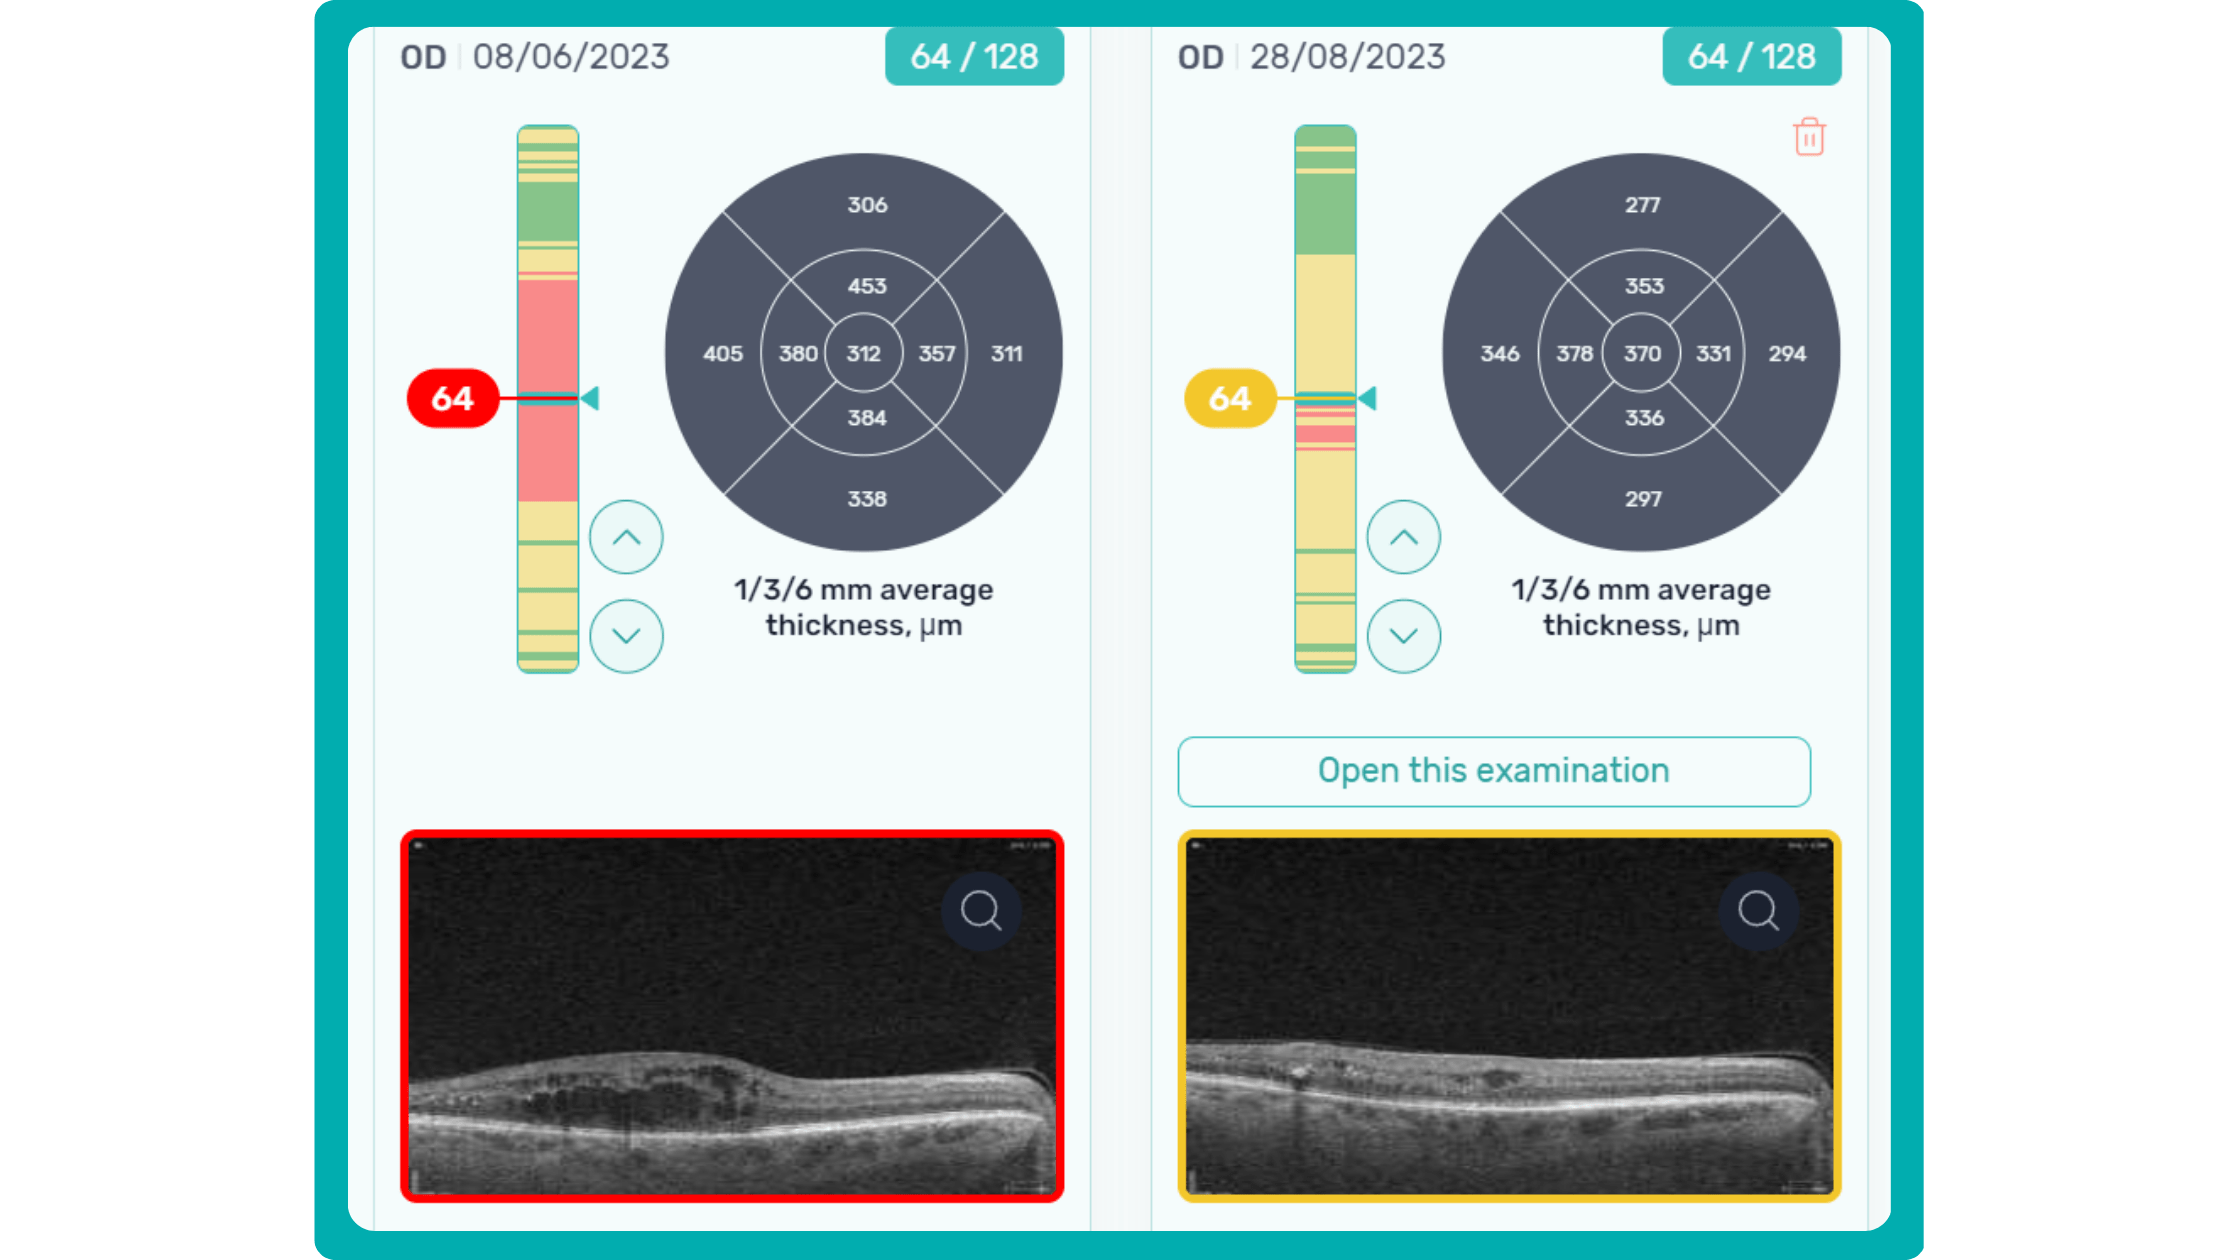

Dr. Maria Sampalis, OD, the owner of Sampalis Eye Care, Rhode Island, utilizes two such programs in her practice. To support her specialization in dry eye management, she employs CSI Dry Eye. Additionally, she uses Altris AI, an AI-powered platform for OCT scan analysis, to provide a second opinion and enhance diagnostic accuracy.

Dr. Sampalis finds that the Dry Eye software allows her and her staff to analyze symptoms and images comprehensively, improving patient care, time savings, and increasing diagnostic precision. See how OCT AI works here.

Her patients also appreciate Altris AI, which analyzes OCT scans for over 70 pathologies and biomarkers while also calculating the risk of developing glaucoma.

Working with specialized software solutions improves diagnostic accuracy and aids in patient education. Visual representations of their conditions, facilitated by these technologies, empower patients with a clearer understanding, leading to increased treatment compliance.

Eye Place, an optometry center in Columbia, also leverages Altris AI, among other cutting-edge technologies. They capture images using the Topcon Maestro2 OCT and use Image Net6 software to export DICOM files to the Altris AI platform.

AI-assisted readings of OCT scans are already helping not only with pathology detection but also with the analysis of its progression or response to treatment. This represents a new approach to monitoring, where practitioners no longer need to sift through various patient notes but can directly compare reports from previous examinations and observe how, for instance, shadowing has changed in micrometers.

To illustrate the point, here is a handwritten referral compared to one of the types of customised OCT report from the Altris AI system, a platform that automates AI-powered OCT scan analysis for 70+ pathologies and biomarkers. This screenshot, in particular, shows segmented retina layers and highlights biomarkers of Dry AMD alongside a comparison of the patient’s macular thickness over visits.

Let’s explore how this applies to a clinical case, such as monitoring a patient with Wet AMD during follow-up visits.

Subsequent follow-up visits will then display the most relevant picture, highlighting the most pertinent biomarkers for tracking a particular pathology (wet AMD in our example) and comparing their volume, progression, or regression through visits.